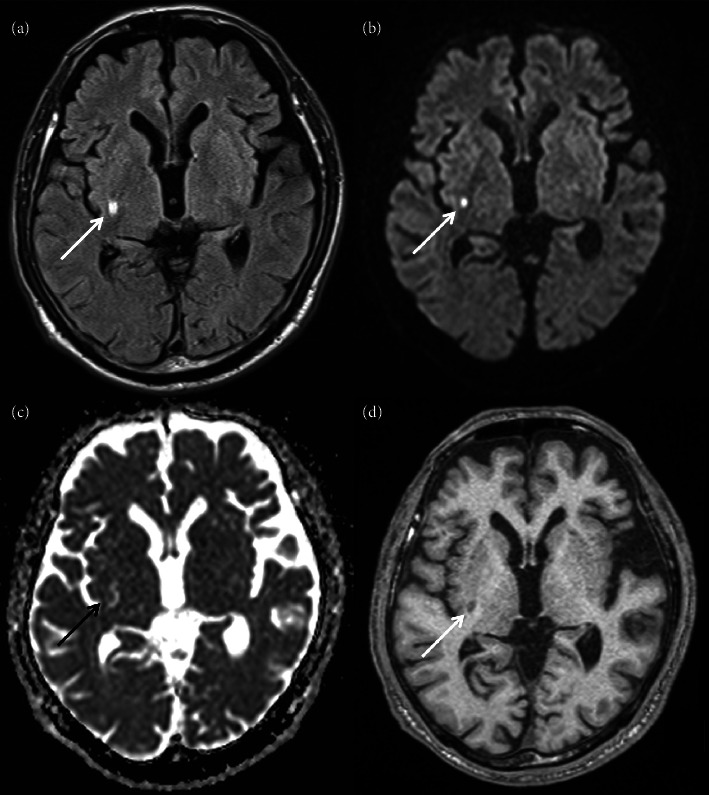

偏曲是缺血性脑卒中中一种罕见的表现,其病变通常位于对侧基底节区。其发病机制尚未完全阐明;然而,它可能与黑质纹状体功能障碍有关。在偏曲患者中,多巴胺转运-单光子发射计算机断层扫描显示对侧纹状体中示踪剂积累减少。此外,在特殊情况下,负责病变位于同侧大脑半球。本病例报告描述了一位84岁的男性,他表现为三周的间歇性,不自主和右肢体扭曲运动。体格检查,患者有右侧血瘀,无其他神经功能缺损。下肢的舞蹈动作比上肢更频繁,当他试图采取某种姿势或进行心算时,就会被激怒。怀疑脑卒中时进行的磁共振成像检测到在透镜状核后部和内囊后肢的右半球亚急性梗死。此外,DAT-SPECT显示右侧纹状体中示踪剂积累减少。他被诊断为腔隙性梗死后给予口服抗血小板药物。在接下来的8个月里,舞蹈动作逐渐减少,最终消失。考虑到出血与缺血性脑卒中在时间上的接近性,在透镜状核和内囊的病变被认为是诱发了同灶性出血。虽然在同裂孔出血患者中的DAT-SPECT发现尚未报道,但该病例提示黑质纹状体多巴胺功能障碍可能与同裂孔出血的发病机制有关。

Hemichorea is a rare manifestation of ischemic stroke whose lesion is typically located in the contralateral basal ganglia. Its pathomechanism has not been elucidated completely; however, it may be related to nigrostriatal dysfunction. In patients with hemichorea, dopamine transporter-single photon emission computed tomography (DAT-SPECT) reportedly displayed decreased tracer accumulation in the contralateral striatum. Moreover, in exceptional cases, responsible lesions were located in the ipsilateral cerebral hemisphere. This case report describes an 84-year-old man who presented with three weeks of intermittent, involuntary, and twisting movements in his right limbs. On physical examination, the patient had right-sided hemichorea without other neurological deficits. The choreic movements were more frequent in the lower limb than in the upper and provoked when he tried to take a certain posture or engaged in mental arithmetic. Magnetic resonance imaging performed on suspicion of stroke detected a right hemispheric subacute infarct in the posterior part of the lenticular nucleus and posterior limb of the internal capsule. Furthermore, DAT-SPECT revealed decreased tracer accumulation in the right striatum. He was administered oral antiplatelet medication after being diagnosed with lacunar infarction. The choreic movements gradually reduced over the next 8 months and eventually disappeared. The lesion in the lenticular nucleus and internal capsule was considered to have induced ipsilesional hemichorea, considering the temporal proximity between the hemichorea and ischemic stroke. Although DAT-SPECT findings in patients with ipsilesional hemichorea have not been reported, this case suggests that nigrostriatal dopamine dysfunction can contribute to the pathogenesis of ipsilesional hemichorea.